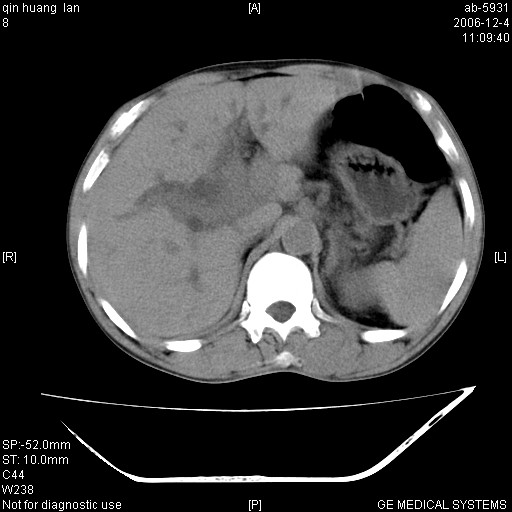

以下是引用qiuleiyu在2006-12-4 19:07:00的发言:[br]1、无基础肝硬化表现。[br]2、左右肝内胆管明显软藤样扩张。[br]3、肝门区肿块,呈现延时花瓣样强化。而非快进快出强化。[br]4、胰头大,然密度较均,未见双管征。[br]5、后腹膜多发淋巴肿大。[br]考虑肝门部胆管ca伴胰头及后腹膜广泛淋巴转移及胆总管扩张。必要时mrcp进一步检查。

以下是引用jinguoji在2006-12-5 13:08:00的发言:[br][br]肝门区胆管细胞癌 并肝门、胰头周围、腹后淋巴结肿大转移。